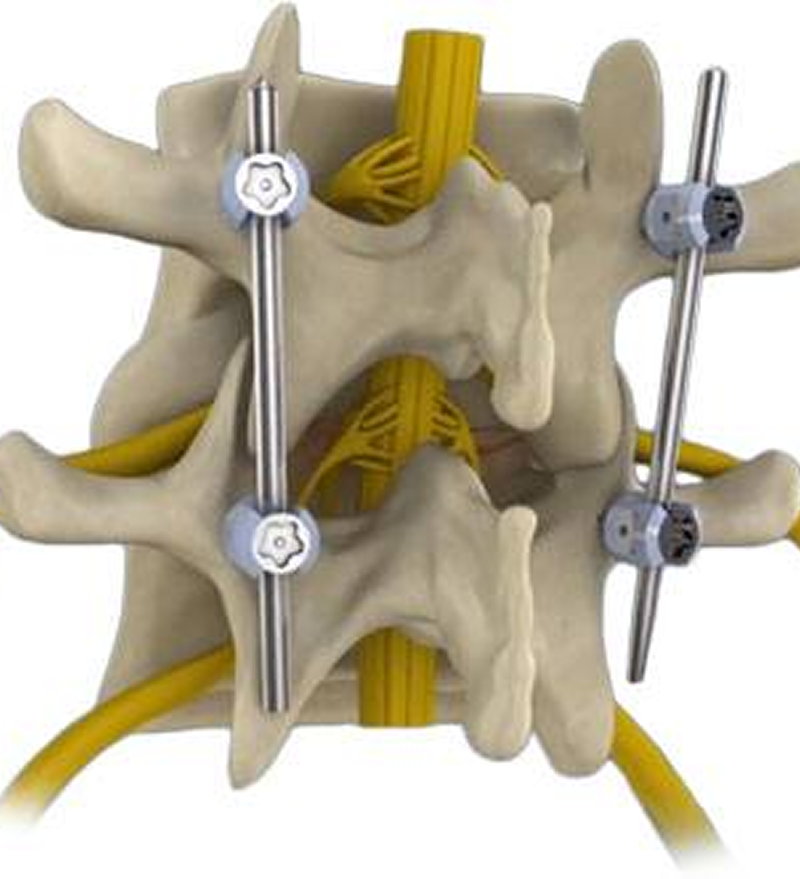

Spinal Fusion

Fuses two or more vertebrae to stabilize the spine. Spinal fusion surgery involves joining two or more vertebrae (spinal bones) together to prevent movement between them, aiming to relieve pain and stabilize the spine. This procedure is often performed when other treatments, like physical therapy or medication, haven't been successful.

Purpose: Spinal fusion aims to stop painful movement between vertebrae, which can occur due to conditions like arthritis, spinal stenosis, or injuries.

Procedure: During surgery, a surgeon may remove the disc between the vertebrae and place bone grafts (from the patient's own body, a donor, or artificial materials) to stimulate bone growth and fusion.

Types of Fusion: There are various types of spinal fusion, including anterior, posterior, and transforaminal lumbar interbody fusion (TLIF), each with different approaches to accessing the spine.

Benefits: Spinal fusion can significantly reduce pain, improve spinal stability, and correct spinal deformities.

Risks and Recovery: Like any surgery, spinal fusion carries risks such as infection, nerve damage, and non-union (failure of bones to fuse). Recovery time varies, but it generally takes several weeks to months, with full recovery potentially taking up to six months.